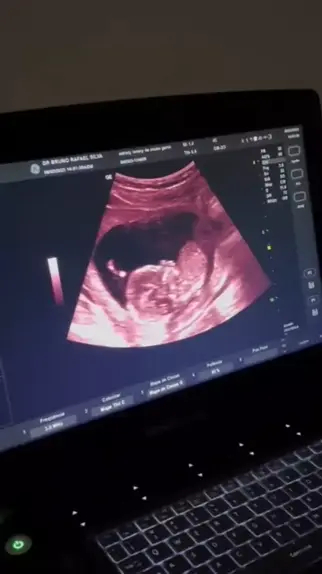

Manu Balançando a mãozinha, ultrason com 16 semanas 😍❤️ #ultrassom #gravidez #Mae #princesa #grávida